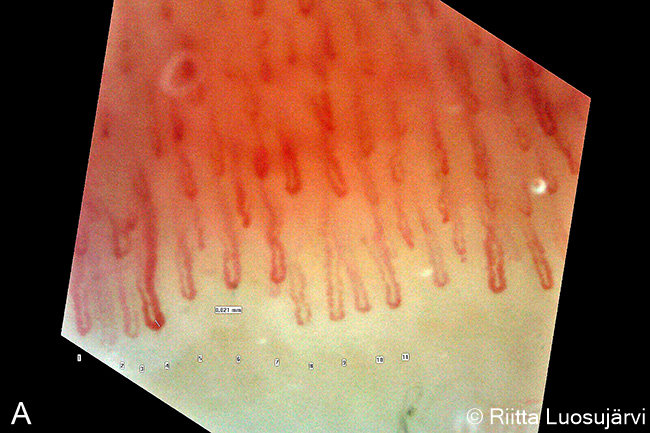

A. Normaalit kapillaarit. Kapillaarit ovat kapeita, ne ovat ryhmittyneet siististi hiuspinnimäisesti vierekkäin, ja niitä on yli 9/mm. Kuvassa nähdään normaalit kynsinauhan kapillaarit 220-kertaisella suurennoksella.